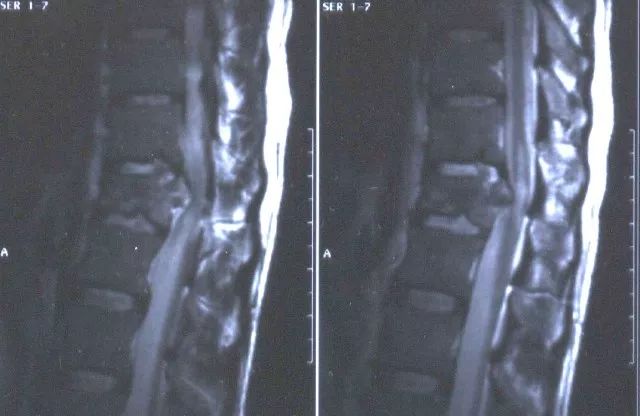

脊髓损伤是一种严重的神经系统损伤,可能导致患者身体功能受损甚至终身残疾,这种损伤通常由于交通事故、运动伤害或疾病等原因引起,而在中国,随着工业化和城市化的快速发展,脊髓损伤患者的数量也在不断增加,这已成为一个严重的公共卫生问题。

1、手术治疗:随着医学技术的不断进步,手术治疗在脊髓损伤治疗中发挥着越来越重要的作用,最新的手术治疗方法包括微创手术和显微手术等,具有创伤小、恢复快的优点,能够最大限度地保护患者的神经功能。